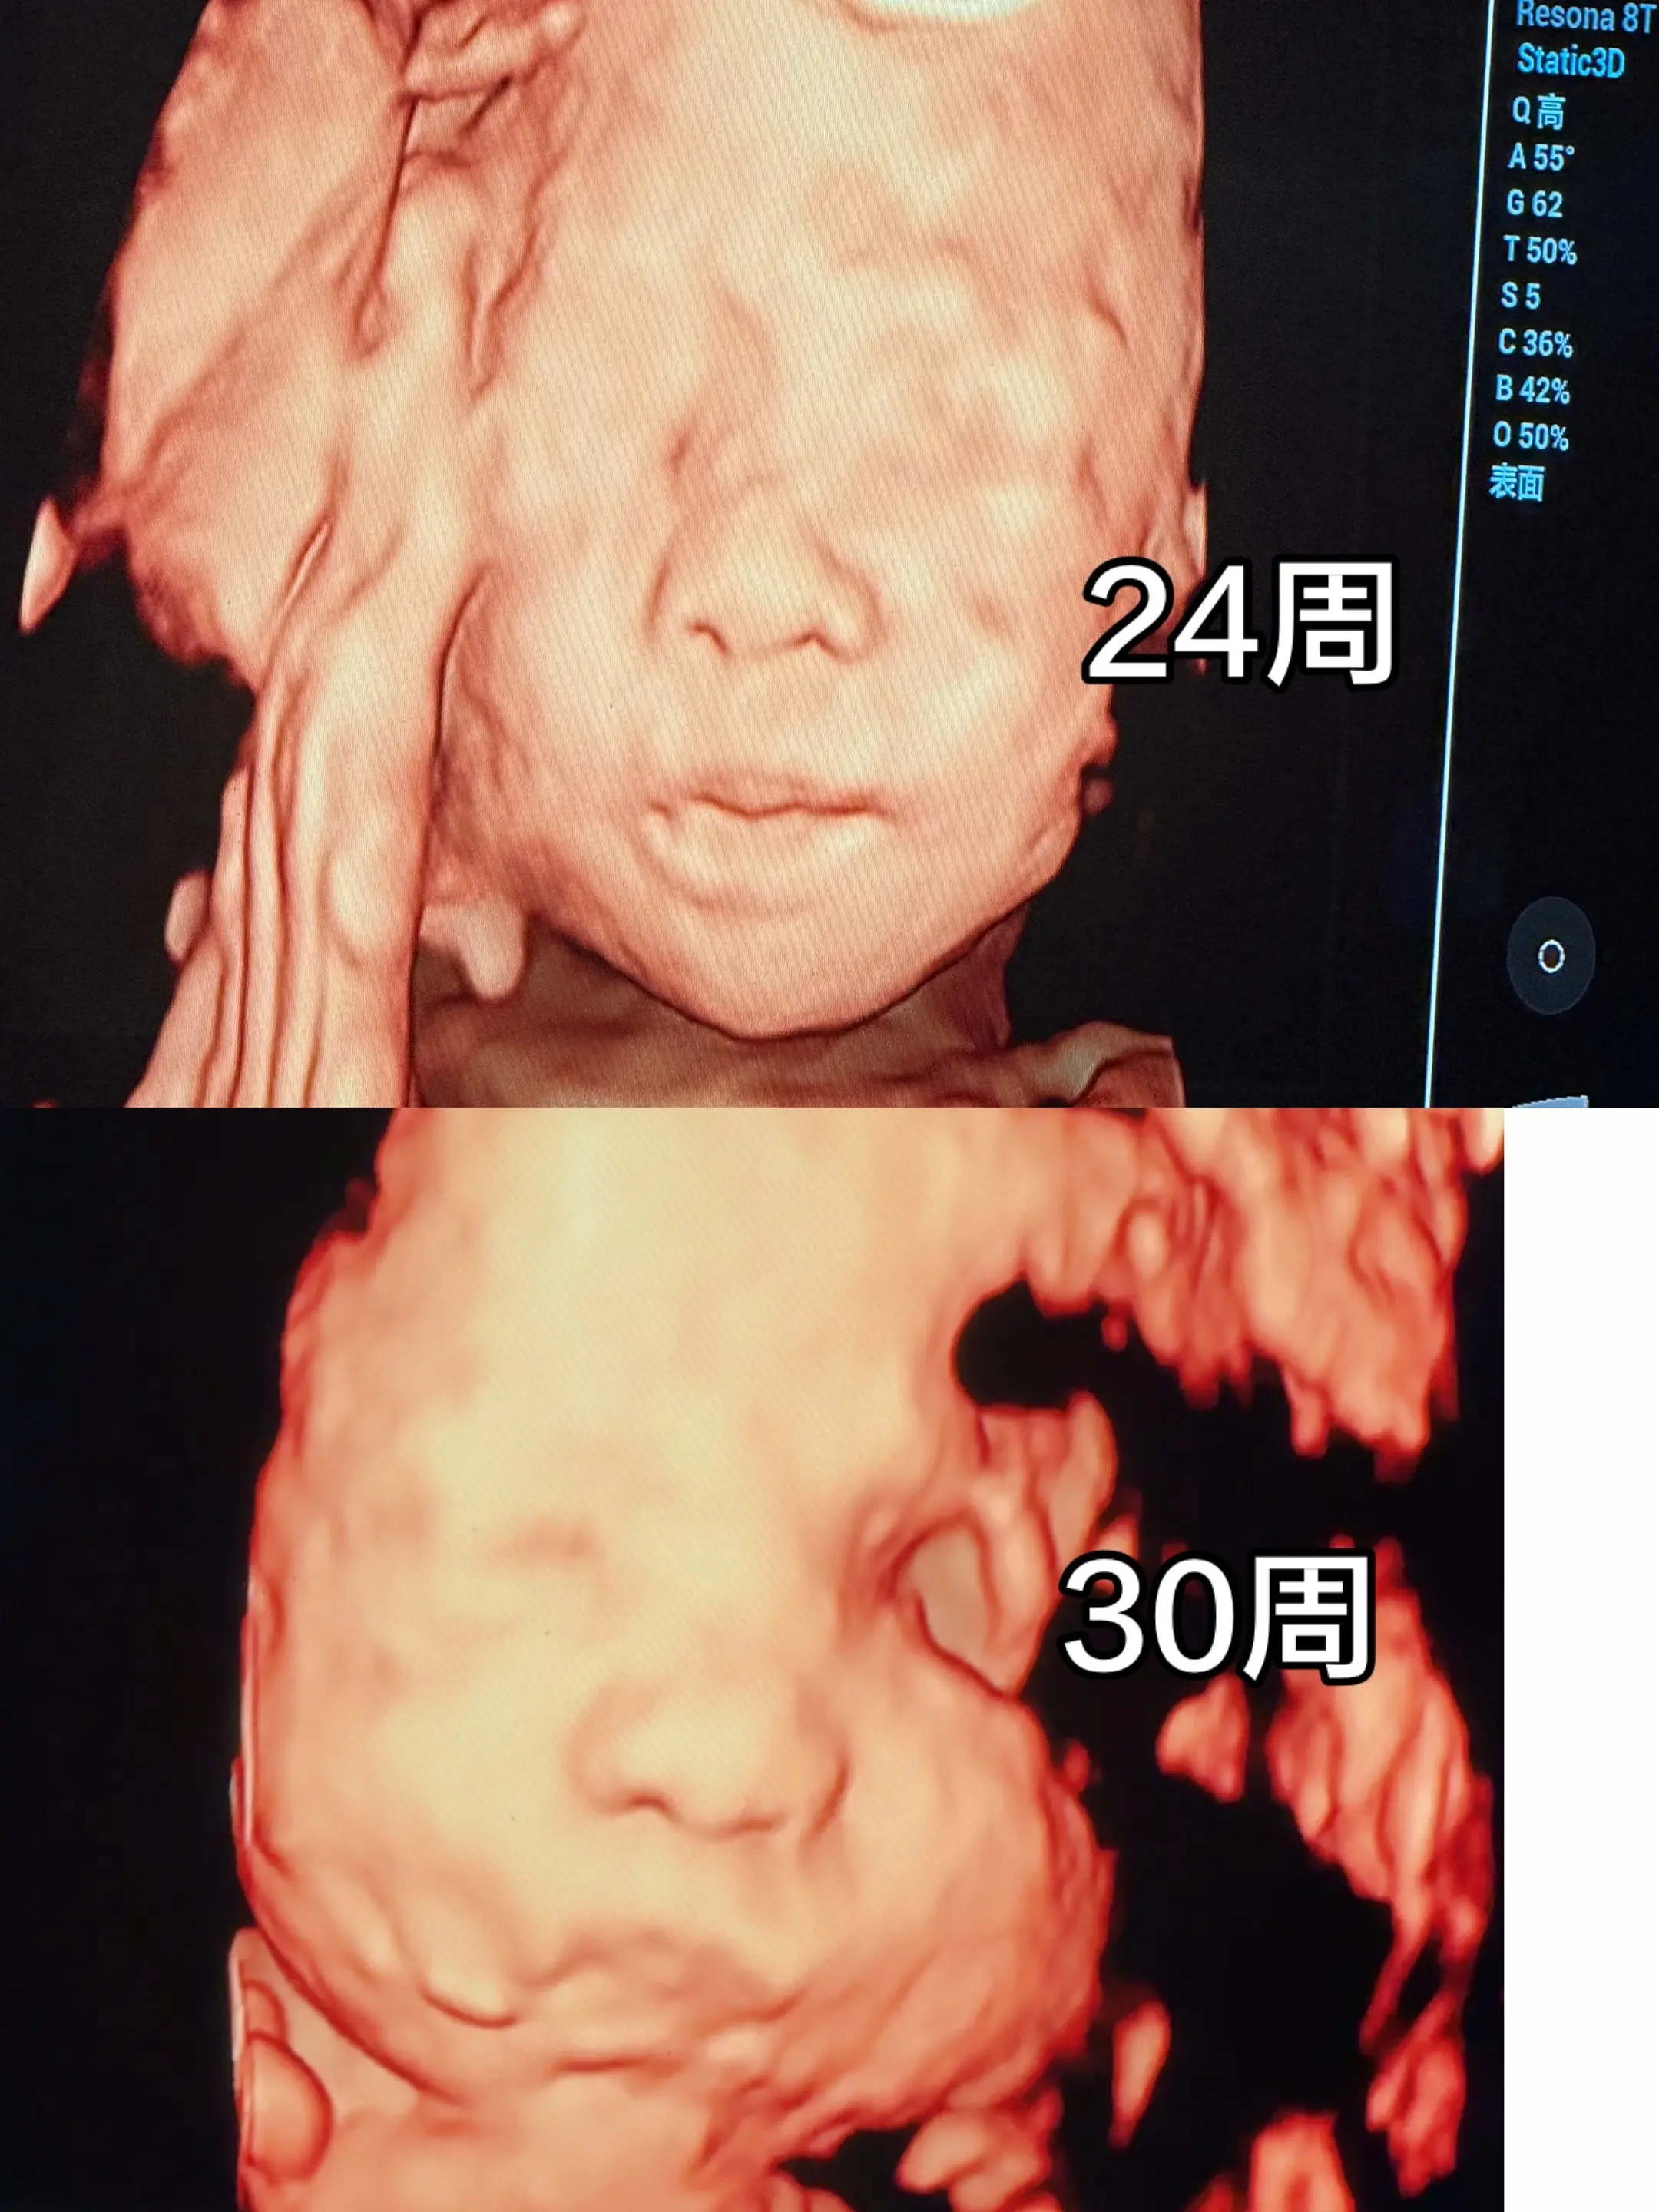

宝宝你的瓜子脸去哪里了😂😂。